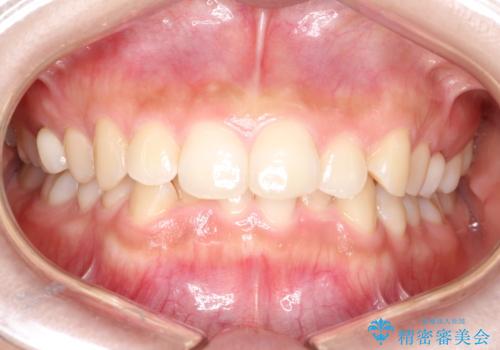

【ワイヤー矯正】前歯のがたがたをなおしたい

- 前歯のがたがたを主訴に来院されました。

叢生量も軽度なため短期間で治療を行っています。